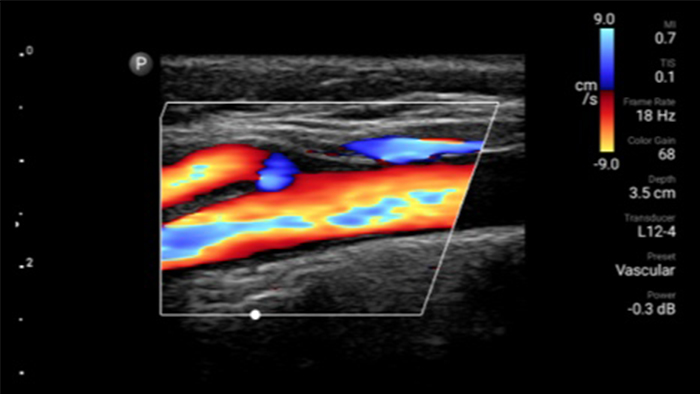

Lumify handheld ultrasound offers images that enhance diagnostic confidence.

See more when it counts

Lumify can help you make real-time decisions with more confidence, from assessment to recovery. Reveal the subtle details of an image, uncover enriched tissue definition with multiple angles and much more.